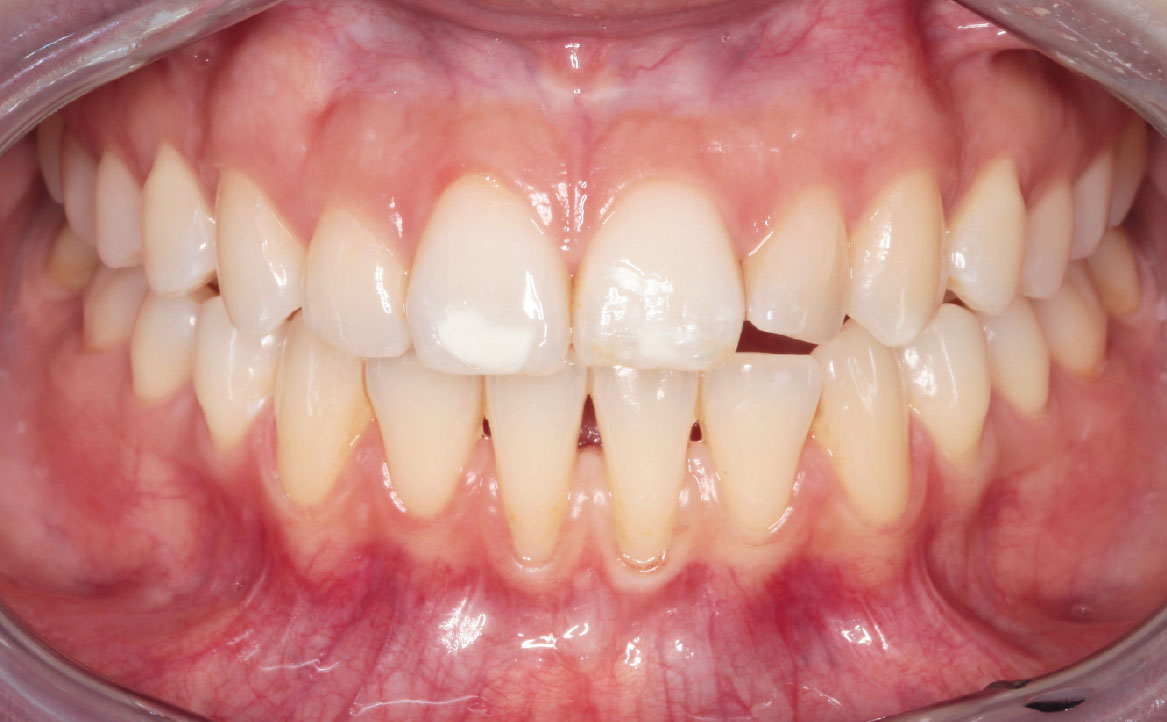

Il caso descritto riguarda una giovane paziente di 31 anni che si è presentata presso l’Unità Operativa di Odontostomatologia dell’Ospedale di Parma per recessioni gengivali di grado I di Miller della superficie vestibolare degli elementi 3.1 e 4.1. La paziente ha riferito deficit di coagulazione congenito e allergia alla mepivacaina.

All’esame obiettivo si è riscontrata scarsità della profondità del vastibolo in zona mandibolare anteriore. Si è deciso perciò di intervenire chirurgicamente eseguendo una vestibuloplastica inferiore con laser Nd:YAG.